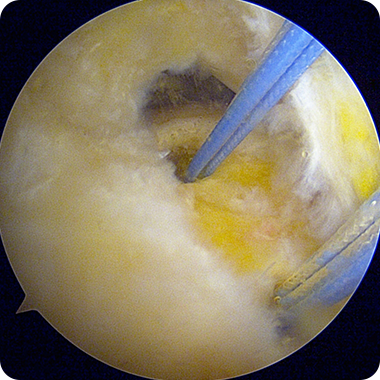

1cm 미만의 절개로 관절내시경을

삽입해 회전근개 파열 부위를

직접 확인합니다.

손상된 힘줄 주변을 깨끗이 정리하고

봉합이 잘 이루어지도록

부착 부위를 준비합니다.